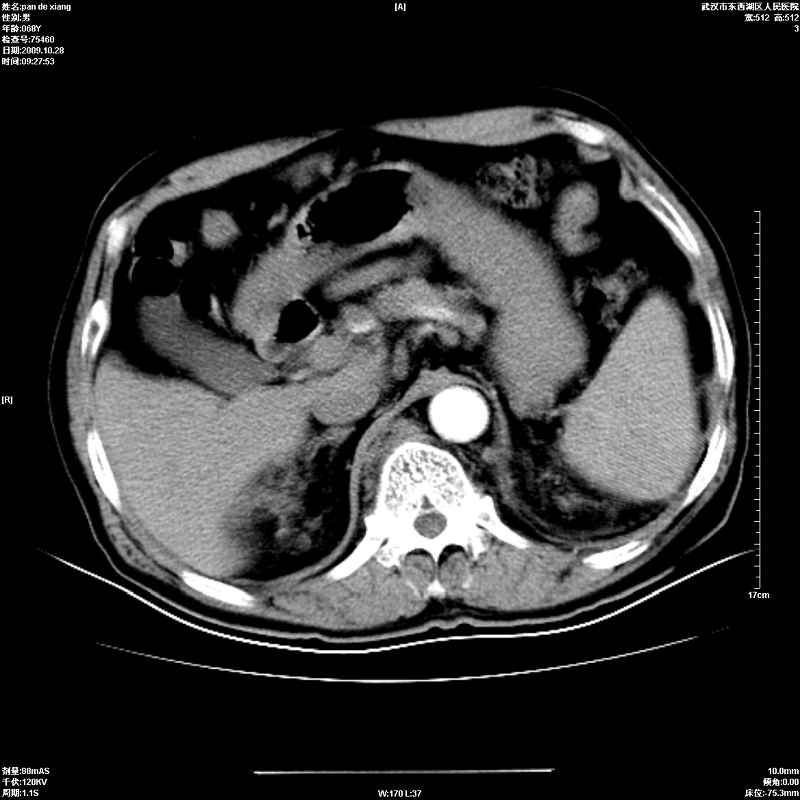

以下是引用杀毒软件在2009-10-28 20:41:00的发言:[br]结合临床考虑---白血病双肾改变或淋巴瘤。

以下是引用zxl51642在2009-10-29 9:59:00的发言:[br]结合临床“单克隆免疫球蛋白血症”,考虑双肾为继发损害并肾功能不全(尿中大量igg及少量iga、igm等大分子免疫球蛋白滤出所致继发损害),椎前软组织肿块为髓外造血。与浆细胞瘤有区别,平扫时有战友说的很清楚。